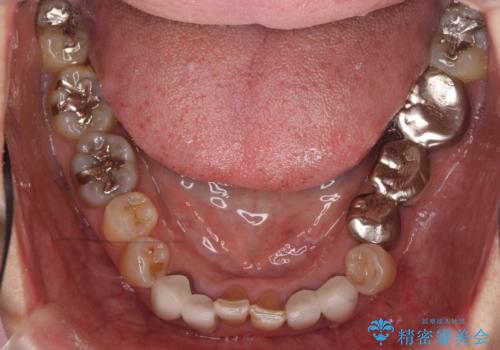

- 前歯の色や形を全体的に綺麗したいといらっしゃった方の症例です。

下顎は左側 4 番目から右側 4 番目までの 8 歯と左下 567 ブリッジをオールセラミッククラウンで補綴し、右下67の銀歯はセラミックインレーによる修復を行いました。